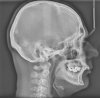

Und hier noch die Röntgenbilder vor einigen Wochen

Anhänge: